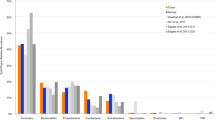

The bacteriome in the cancer tissue and the control tissue were examined at different taxonomic levels. We identified differences in the distribution of eight phyla and eighteen genera (Fig. 1B,C). The top three phyla in the cancer samples were: Firmicutes, Bacteroides and Spirochetes. In normal healthy control tissues, the predominant phylum was Firmicutes followed by Spirochetes and Actinobacteria. The cancer tissue demonstrated a decrease in the relative abundance of Firmicutes coupled with an increase in Bacteroidetes relative to controls. Also, Actinobacteria showed a decrease in abundance in the cancer tissues in comparison with the normal controls. We did not find any statistically significant associations between clinical variables including anatomic subsites, tumor size and nodal status and microbiomic profiles in cancer tissue. The PCA (principal component analysis) plot for the groups is illustrated in Fig. 1D.

Oral cancer bacteriome differs between matched tumor surface and deep tumor tissue samples

The bacterial community of matched tumor surface mucosa and tumor tissue differed significantly, both at the community level (Fig. 4A) as well as at taxonomic levels (Fig. 4B,C). The PCA plot for the groups is illustrated in Fig. 4D. There was a significant difference in the abundance of phyla Bacteroidetes and Fusobacteria on tumor surfaces illustrating a lesser proportion of the former and higher proportion of the latter in comparison to matched cancer tissues. Especially, the abundances of taxa belonging to genera Porphyromonas, Enterobacteriae, Neisseria, Streptococcus and Fusobacterium were significantly elevated on the tumor surfaces: Prevotella, Treponema, Sphingomonas, Meiothermus and Mycoplasma genera were significantly more abundant in matched deep tumor tissue samples (Fig. 5). Twenty-four metabolic pathways were found to differ between tumor surface and deeper tissue (Fig. 6). The most abundant pathways were those related to fatty-acid biosynthesis, carbon metabolism and amino-acid metabolism on the tumor surface: carbohydrate metabolism and organic polymer degradation were elevated in cancer tissues.

Differences in WMF and tumor tissue bacteriomes

Because of the potential of WMF, through its microbiota, to be a source of a biomarker for the presence of oral cancer, we evaluated whether microbial profiles of WMF reflected those of cancer tissue. The bacteriome in tumor tissue and paired WMF samples from patients with oral cancer differed significantly in terms of overall community structure and a PLS-DA plot demonstrated that bacterial profiles tended to cluster separately (Fig. 7A). Yet the overall composition of various taxa remained similar between the two sets of samples at phylum and genus level (Fig. 7B,C). The PCA plot for the groups is illustrated in Fig. 7D. Nevertheless, statistically significant differences between bacterial communities of WMF and tissue were still detected: abundances of four taxa belonging to the genera Streptococcus, Lactobacillus and Bacteroidales (Fig. 8A) and acetoin biosynthesis pathway were significantly enriched in the tissue (P < 0.01) (Fig. 8B).

The bacteriome of WMF can reflect microbial communities of the oral cavity as a whole, as both hard and soft tissue surfaces are constantly bathed in WMF, from which organisms are detached by normal movements within the mouth85. Some recent studies have compared the microbiome of WMF in oral cancer patients to control subjects42,86,87 but no comparisons between WMF microbiome and cancer tissues has, to our knowledge, been published. Our data illustrate that the composition of the various phyla and genera in WMF of OSCC patients remained similar to each other at taxonomic and metabolic levels except in the elevated abundances of Streptococcus, Lactobacillus as well as Bacteroides and acetoin biosynthesis respectively. However, it should be noted that the communities associated with WMF and tumor tissue were set apart significantly in the PLS-DA plot. Our data suggest that the WMF bacteriome does partially reflect the tissue bacteriome and hence has the potential to be developed as a biomarker for prediction of disease status and prognosis.